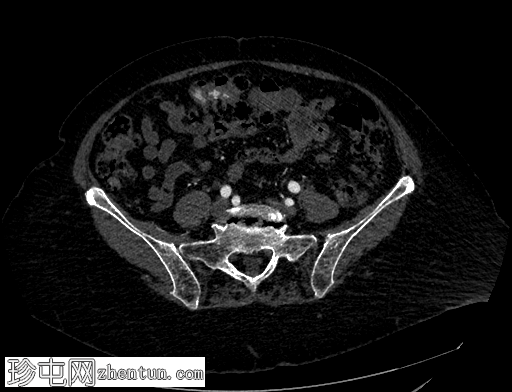

轴位增强扫描

动脉期

横结肠中段可见一憩室,动脉期开始出现异常造影剂外渗,门静脉期增多,憩室腔内亦可见造影剂外渗,提示憩室出血伴活动性动脉出血。

患者既往有结肠憩室炎病史,此次因新鲜下消化道出血就诊。行CT血管造影以确定出血部位和出血来源。出血始于乙状结肠憩室,腔内渗出的造影剂与乙状结肠腔内的造影剂相连。随着造影剂显影的进行,憩室逐渐被完全充盈,乙状结肠腔内渗出的造影剂增多,符合活动性动脉出血的表现。